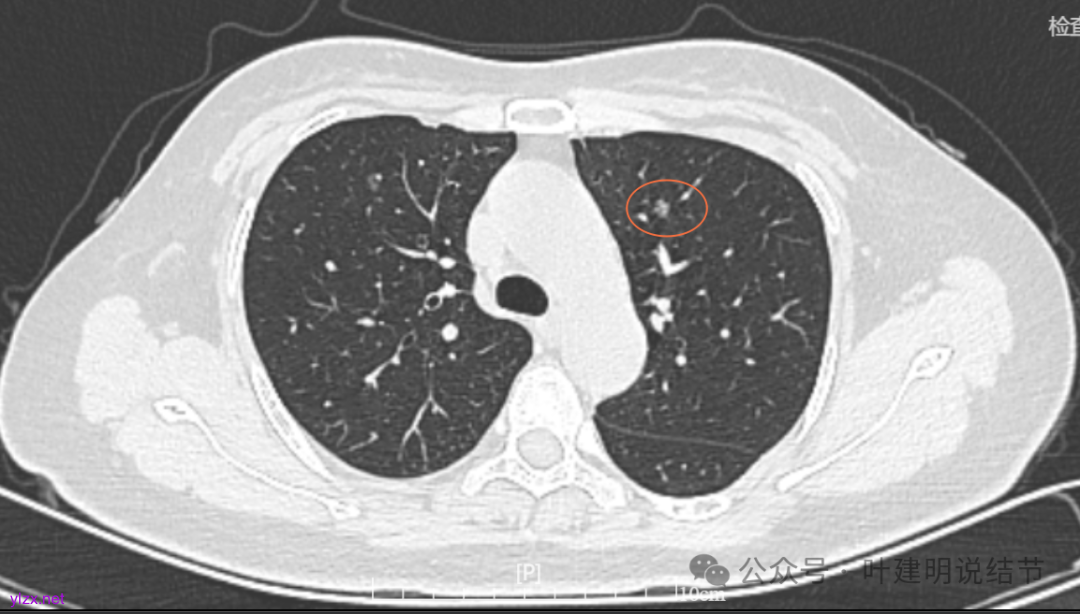

7.2022年11月1日B医院复查ct,显示肺结节0.89*0.51cm。其余变化不大。

8.2023年1月B医院复查ct,显示最大肺结节0.85*0.73cm,其余变化不大。

9.2023年4月复查ct,显示最大肺结节0.79*0.72。2023年3月短暂去某地疗养一月。

10.2023年11月28日复查CT,显示最大结节0.8*0.7cm。

11.2024年9月复查,显示最大结节0.81*0.72。

12.2025年4月复查,显示最大结节0.9*0.7。 另外,看几次报告,多发磨玻璃结节数量在上升,从2022年的3个到2025年的7个。

我们发现其实各病灶与三年前比说不上显著进展。

两肺多发磨玻璃结节,主病灶混合密度且有小血管进入,表面不平有毛刺,考虑微浸润性腺癌或浸润性腺癌可能性大,其余部分考虑原位癌或微浸润性腺癌,部分考虑肺泡上皮增生或不典型增生可能。总体上对比2022年说不上太明显的进展。但对于是否手术来讲,我仍倾向当年的意见,左侧的可以考虑近期亚肺叶(个人倾向楔切)切除,右侧的先随访,以后有进展并风险增加再考虑干预处理。因为要拉长两次手术的间隔,这样对机体的创伤与恢复更加有利一些。若定要仍不开刀,则建议要4-6个月复查,不过个人不太主张过于保守随访,对于像主病灶这种有少许实性成分的,不能保证肯定安全。意见供参考!